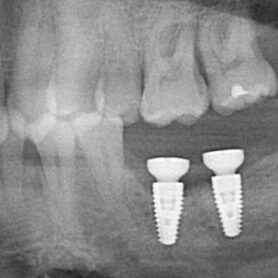

I did explain to him the TiBase design has a very narrow titanium cylinder, and this is the cross section that failed. It is not difficult to understand this mechanism of failure when the size of the crown is examined. Significant torsional loading will occur at the point of the failed titanium cross section when under occlusal function. The pictures below visualize this very well. As this restoration failed very quickly, I would anticipate a similar problem with #18, at some future point, as I suspect they were restored with similar abutments. #18 probably takes more load than #19 due to its posterior position.